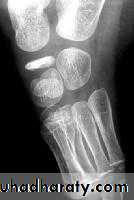

Pain and limitation of joint movement are the usual complaints. Tenderness is sharply localized to the affected bone.X-rays show the characteristic increased density,accompanied in the later stages by distortion and collapse of the necrotic segment.

Examples of crushing Osteochondritis are Freiberg's diseases of the metatarsal ; Kohler's disease of the navicular ; Kienbock's disease of the carpal lunate ; Panner's disease of the capitulum and Scheuermann's disease (vertebral Osteochondritis ).